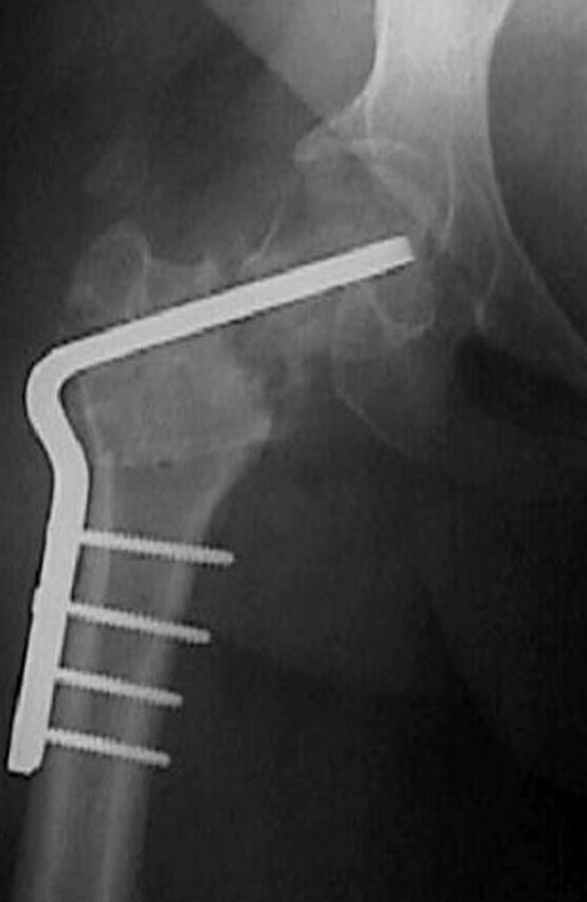

Несколько снимков из моей коллекции, чтобы разьяснить, почему мы до сих пор делаем различные варианты остеотомии.

На рисунке N1 предоперационный план лечения ложного сустава шейки бедра- линия ложного сустава, угол и направление введения импланта, клиновидная остеотомия в градусах и миллиметрах, второй снимок после коррекции, расчет, на сколько удлиняется конечность и размеры импланта;

N3 рисунок окончательный снимок, после операции моя рентгенограмма должен выглядеть примерно как эта картина. На N4 снимке клин перед удалением; N5 послеоперации 3 нед.; N6 окончательная рентгенограмма.

варус при проксимальном отделе 95 градусной пластиной.

Отправитель: Djoldas Kuldjanov 23 Ноябрь 2004, 18:21

пластическая модель; и коррекция бедра аппаратом Илизарова.